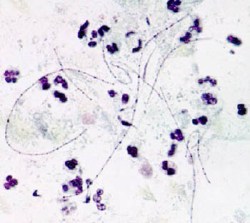

Фото грибок - возбудитель фарингомикоза под микроскопом

Фарингомикоз — поражение слизистой оболочки глотки грибом Leptotrix buccalis.